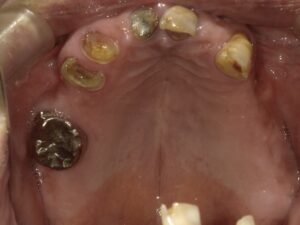

初診時の写真です。

上顎の歯が虫歯でほとんどなくなってしまっています。

上下の歯で噛めるところがありません。

上顎の奥歯は抜いてあるので噛めません。

上顎は当時は歯の形を保っている部分は3本しかありませんでしたが、

今は13本の人工歯が入っており、左右どちらでも噛むことができます。